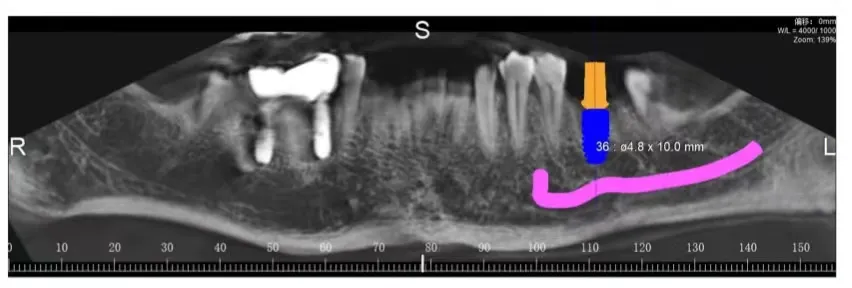

患者骨密度图像

海德堡联合口腔的种植牙概念一直是以修复为导向,依靠德国全数字化微创种植技术,可以明确的标示出神经与血管的位置,根据每一个人每一颗牙齿的骨质分析,精确模拟出种植体种植的方向、角度、深度,将各种数据精准的控制在安全范围内。

可以极大的避免种植体在骨头里边的松动,保证取得一个好的骨结合的结果。

数字化种植方案标识出神经、血管、种植体的位置

在德国全数字化种植技术的引导下,可以将种植手术的精准度、高效性、微创性瞬间提升,毕竟“创伤越小,术后的风险越低”。